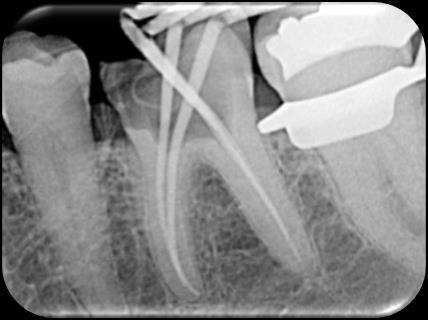

Dr. Dhiraj Arora: A Simple Sequence for Successful Root Canal Treatment Outcomes (EN)